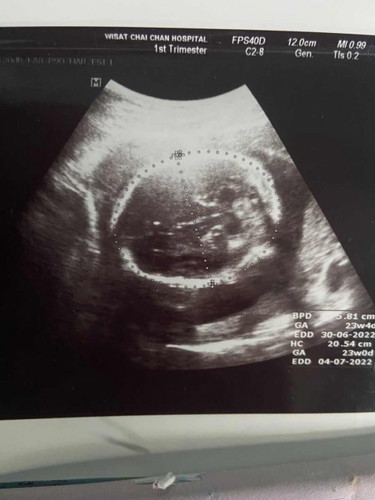

พอจะดูออกไหมคะว่าเพศอะไร หมอบอกแค่ว่าไม่เห็นไข่ ตอนนี้ใกล้คลอดแล้ว เตรียมของไม่ถูกเลยค่ะ ไม่มั่นใจ